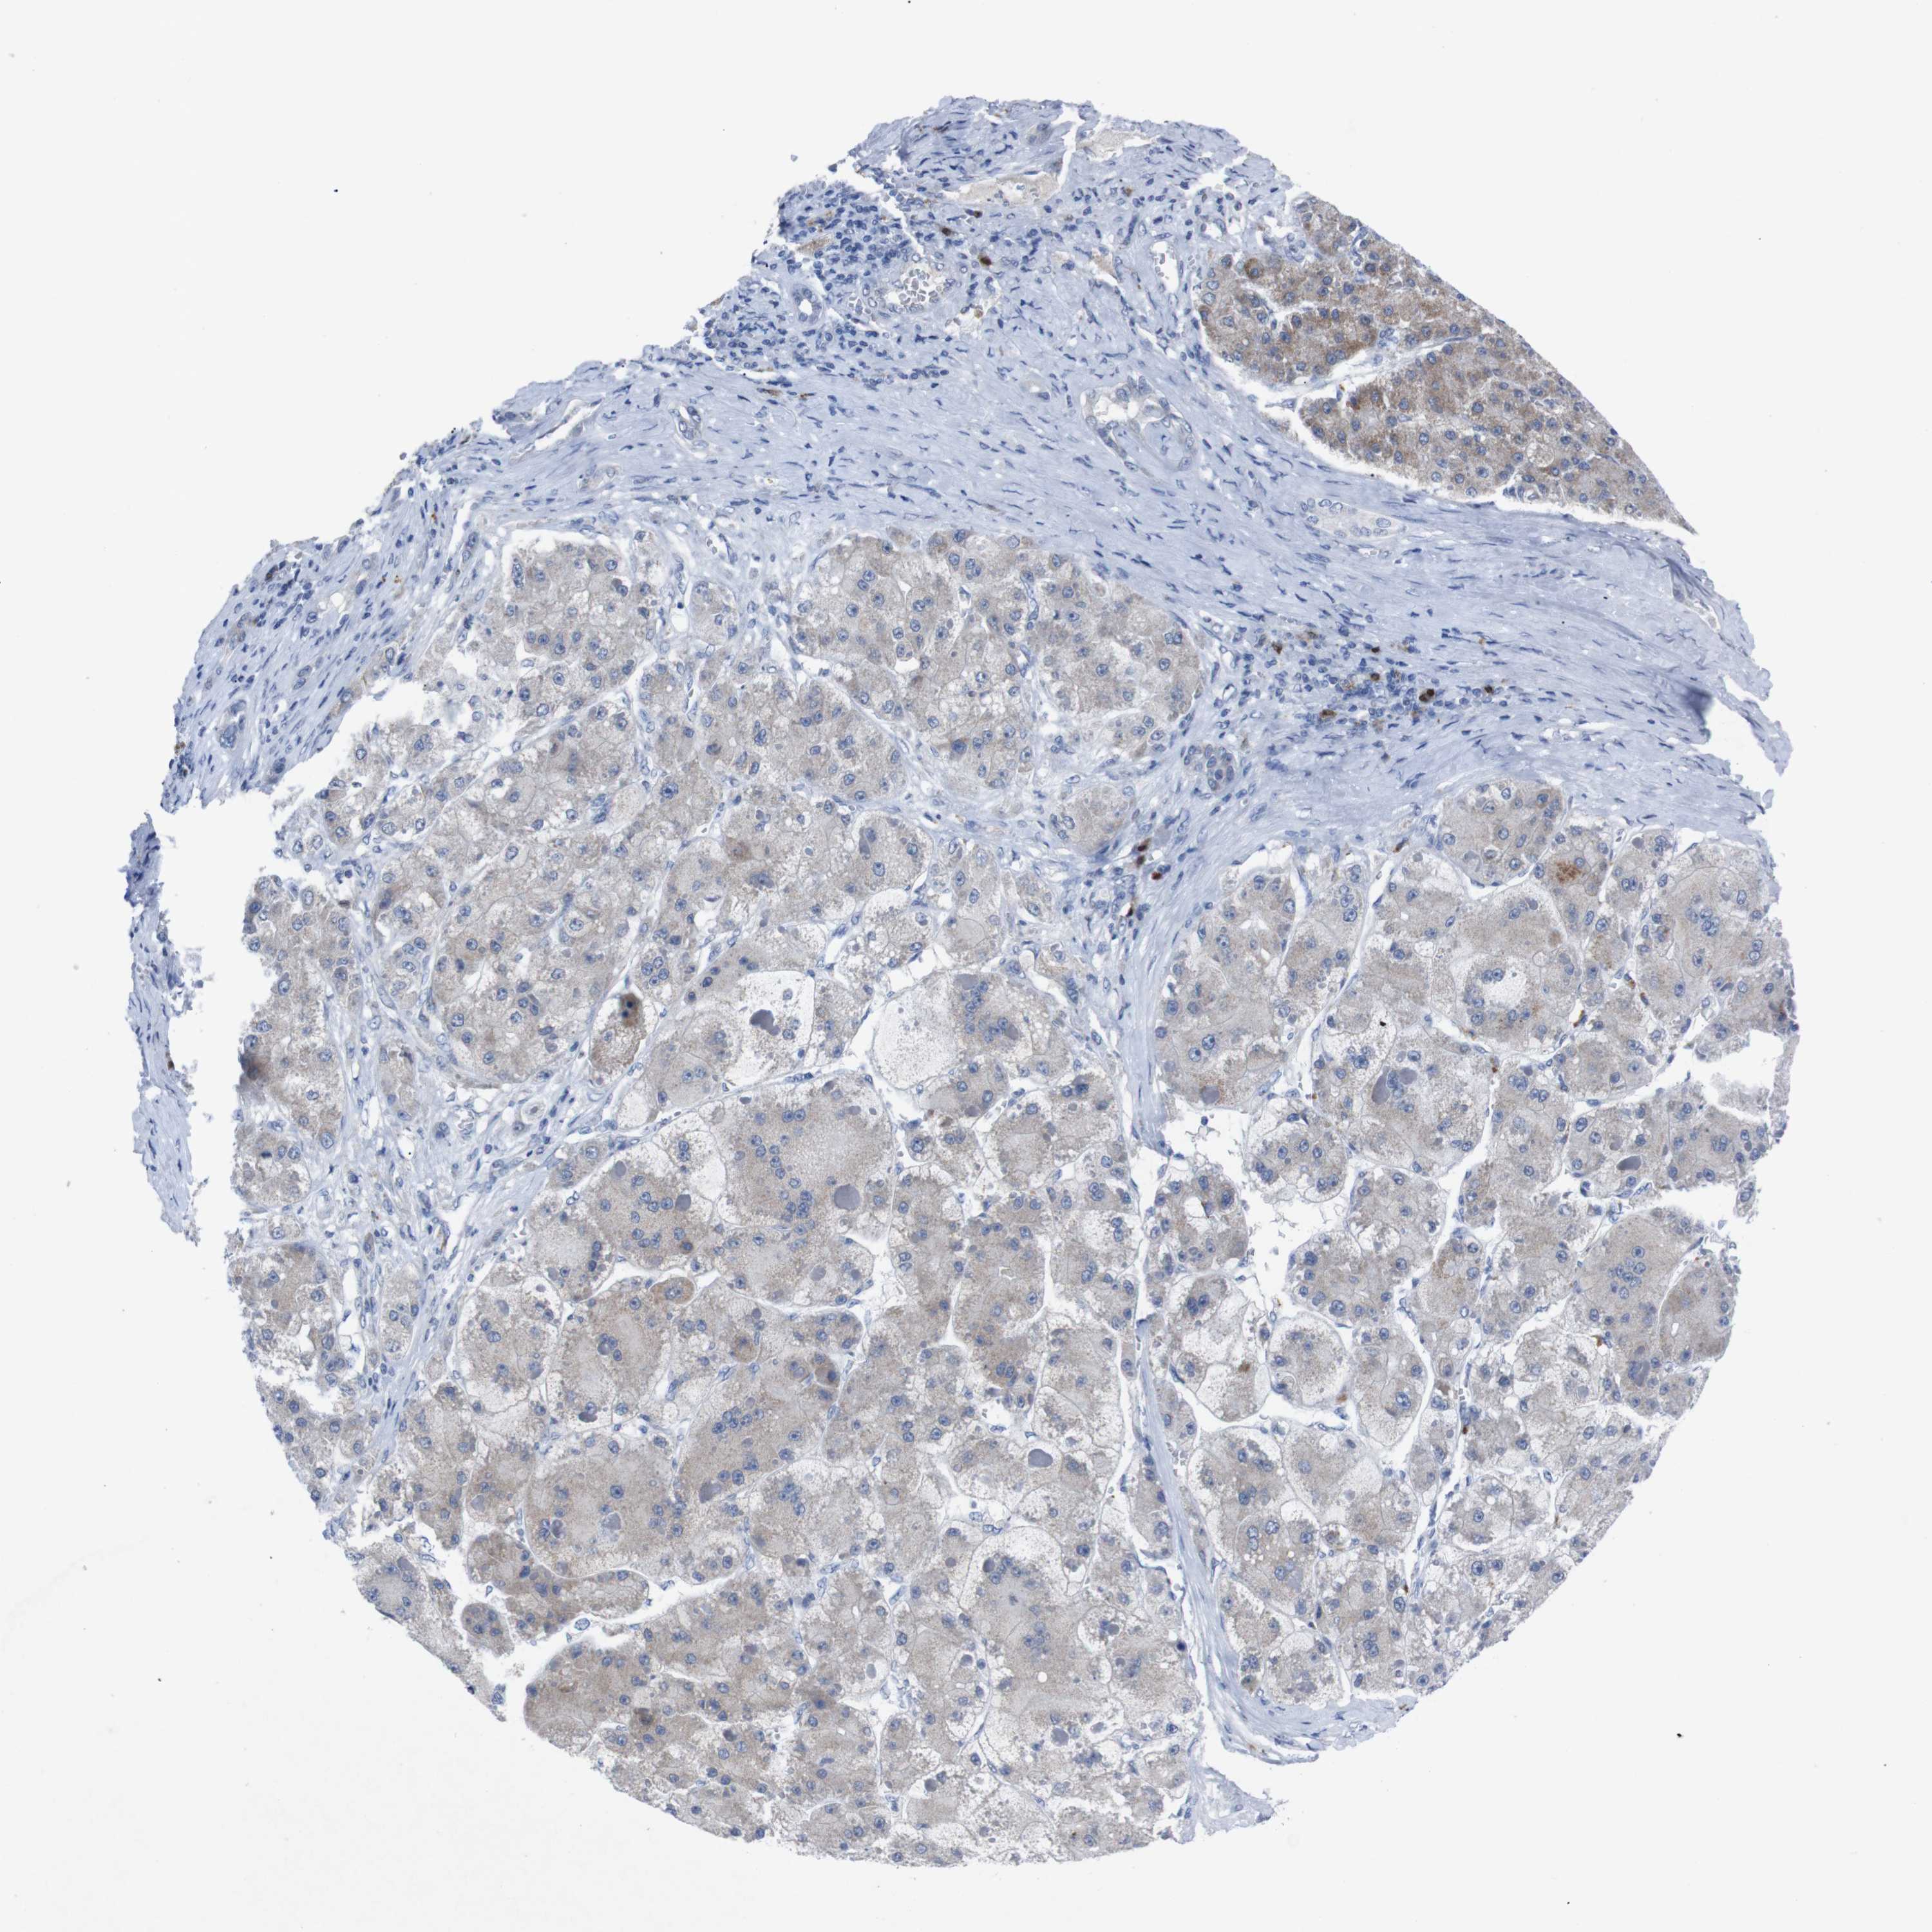

LIVER CANCER - Protein expressioni

A mouse-over function shows sample information and annotation data. Click on an image to view it in a full screen mode. Samples can be filtered based on level of antibody staining by selecting one or several of the following categories: high, medium, low and not detected. The assay and annotation is described here.

Note that samples used for immunohistochemistry by the Human Protein Atlas do not correspond to samples in the TCGA dataset.

Antibody stainingi

Antibody staining in the annotated cell types in the current human tissue is reported as not detected, low, medium, or high, based on conventional immunohistochemistry profiling in selected tissues. This score is based on the combination of the staining intensity and fraction of stained cells.

Each image is clickable and will lead to virtual microscopy that enables deeper exploration of all samples and also displays staining intensity scores, fraction scores and subcellular localization as well as patient and tissue information for each sample.

Antibody HPA002038

Antibody HPA002698

Antibody CAB013508

Staining

High

Medium

Low

Not detected

Intensity

Strong

Moderate

Weak

Negative

Quantity

>75%

75%-25%

<25%

None

Location

Nuclear

Cytoplasmic/membranous

Cytoplasmic/membranous,nuclear

Cholangiocarcinoma

Carcinoma, Hepatocellular, NOS